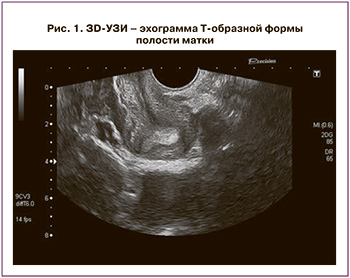

К классу UI относят редчайшую Т-форму полости матки, повышающую риск привычного невынашивания беременности или бесплодия из-за уменьшенного объема полости матки. 3D-критериями стали: неизмененный НКМ, уменьшение поперечного размера матки, Т-форма полости матки с уменьшением ее объема в 3–4 раза в сравнении с нормой. Диагностируется тол ко при отсутствии изменений миометрия, инициирующих сужение полости (рис. 1). Двум пациенткам с привычным невынашиванием произведена резекция латеральных стенок полости петлей биполярного гистерорезектоскопа с последующей терапией, направленной на профилактику образования синехий, а также гормональная терапия КОК сроком 6 месяцев, после чего обе пациентки самостоятельно забеременели, обе беременности завершились самопроизвольными неосложненными срочными родами.